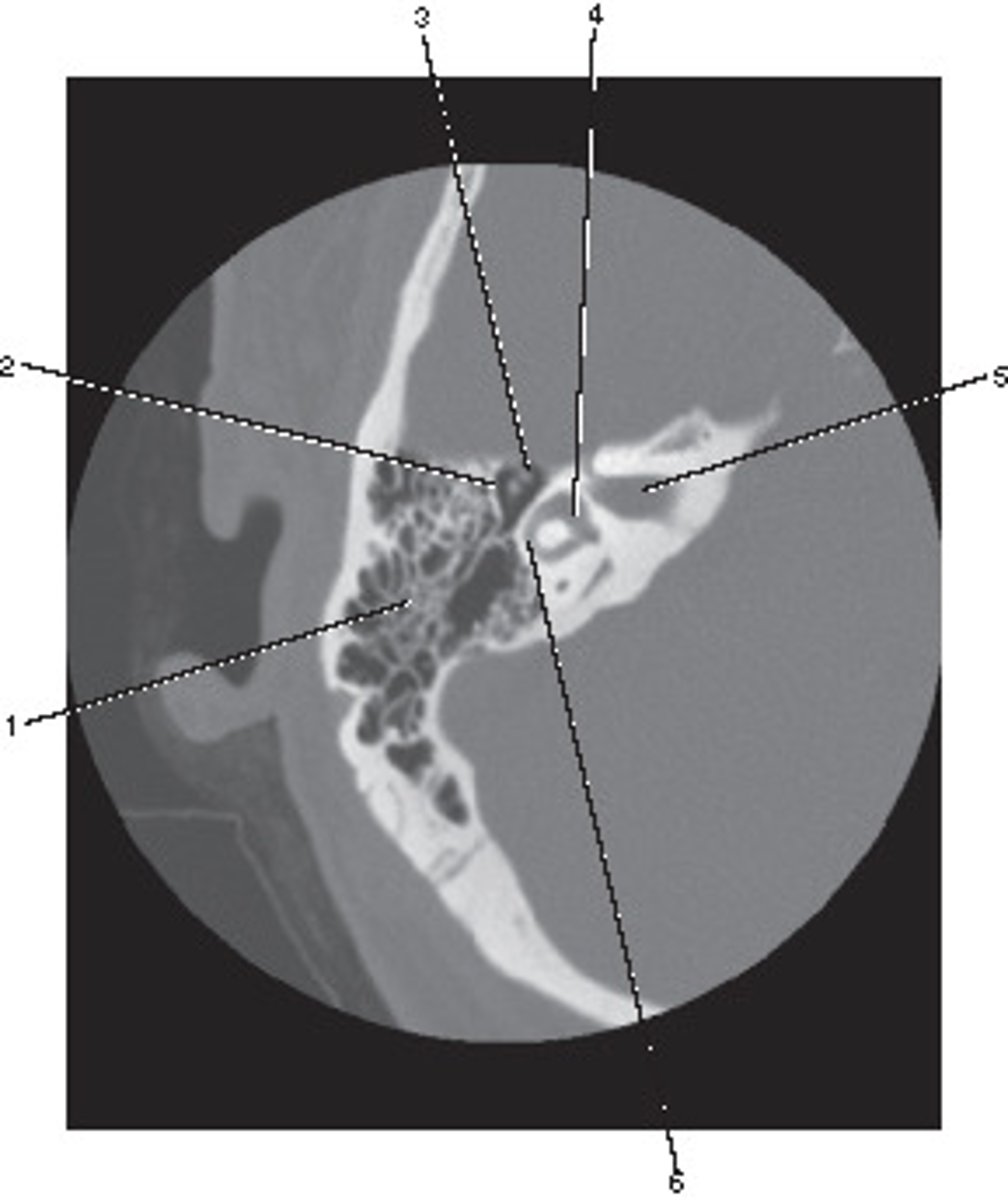

Which number corresponds to the vestibule?

<p>Which number corresponds to the vestibule?</p>

Semicircular Canal

Number 4 corresponds to which of the following?

<p>Number 4 corresponds to which of the following?</p>

Number 2 corresponds to which of the following?

<p>Number 2 corresponds to which of the following?</p>